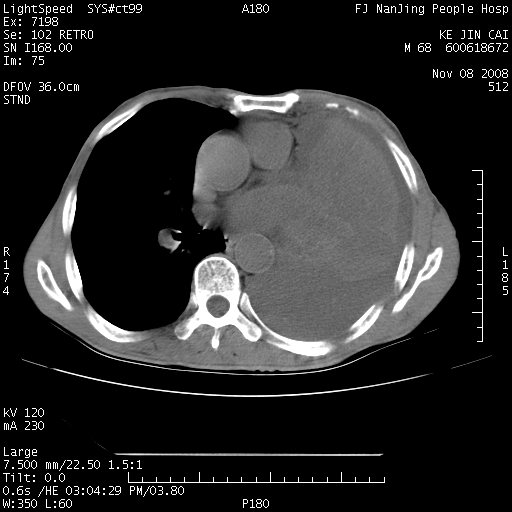

是个很有看头的病例,咋人气那么不旺?没多少人兴趣呢?这个病例几大怪:1   恶性肿瘤侵犯心肌左房怪,心肌一般不会被恶性肿瘤侵犯吧?2   左下肺均匀实变怪,内无含气,有别一般不张实变,含气肺泡完全为液体取代,而非一般不张实变的肺萎陷,冷不丁还以为是肿大的脾脏3   肿瘤本身怪,像tb肺不张4   这么有看头的病例没人气怪。呵呵。

左肺恶性肿瘤侵犯肺动脉,左心房内瘤栓,胸膜转移。

左肺恶性肿瘤侵犯肺动脉,左心房内瘤栓,胸膜转移,少见,学习了。